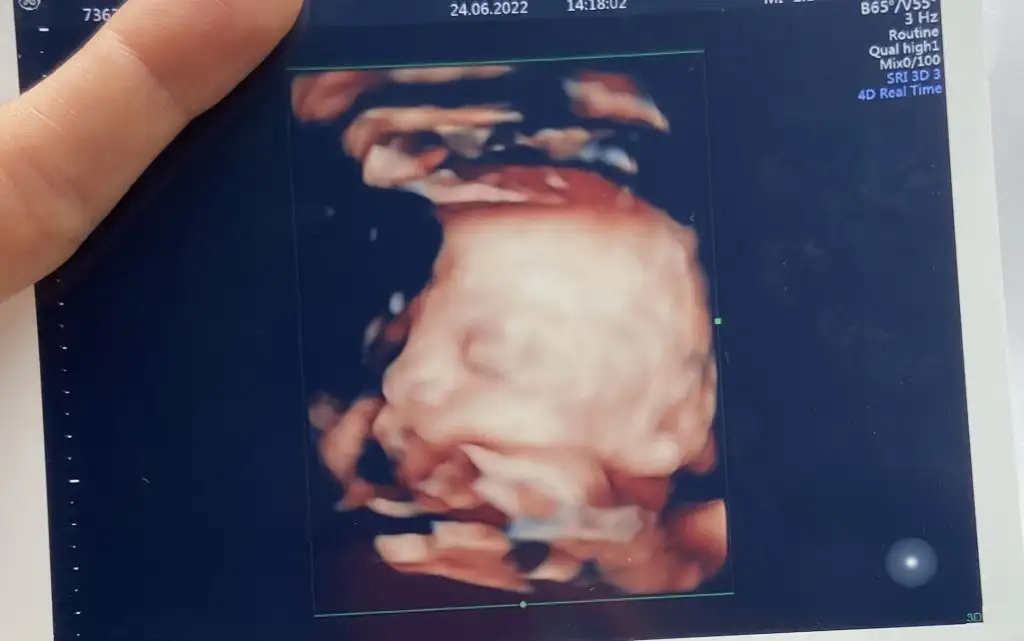

Bir de fotoğraf bırakıyorum size, karnıma bastırdı etti ama tam olarak göremedik net❤️